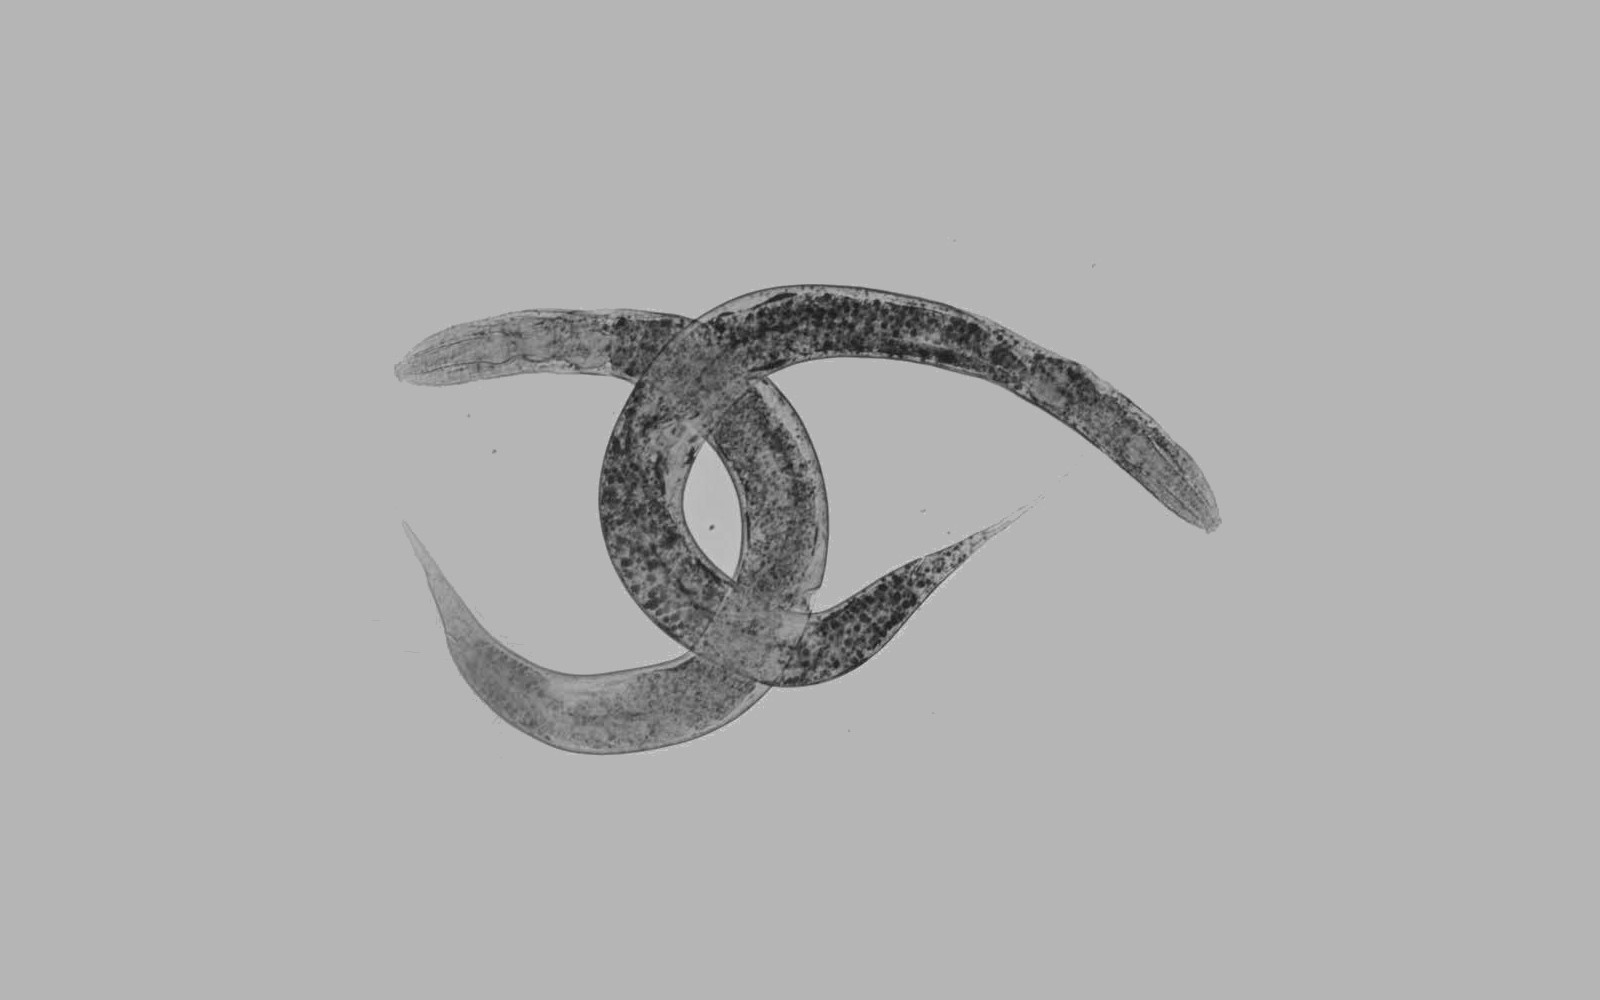

* Explicación de la imagen: Dos gusanos C. Elegans tintados para detectar lípidos (en negro) durante el estudio. Foto: Institut de Neurociències UAB